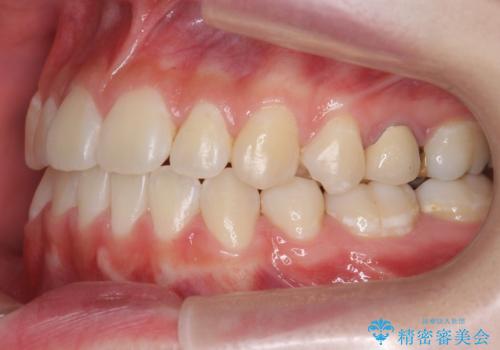

受け口 親知らずを取り込む矯正治療

下の小臼歯を抜歯しましたが、その代わり下の親知らずを残して咬ませたので、歯の数は変わっていません。

左上奥歯は、矯正後セラミックインレー修復を行なっています。

今回は左下の小臼歯を1本抜歯してるのと、手術を行なって親知らずを顎に収めることができました。